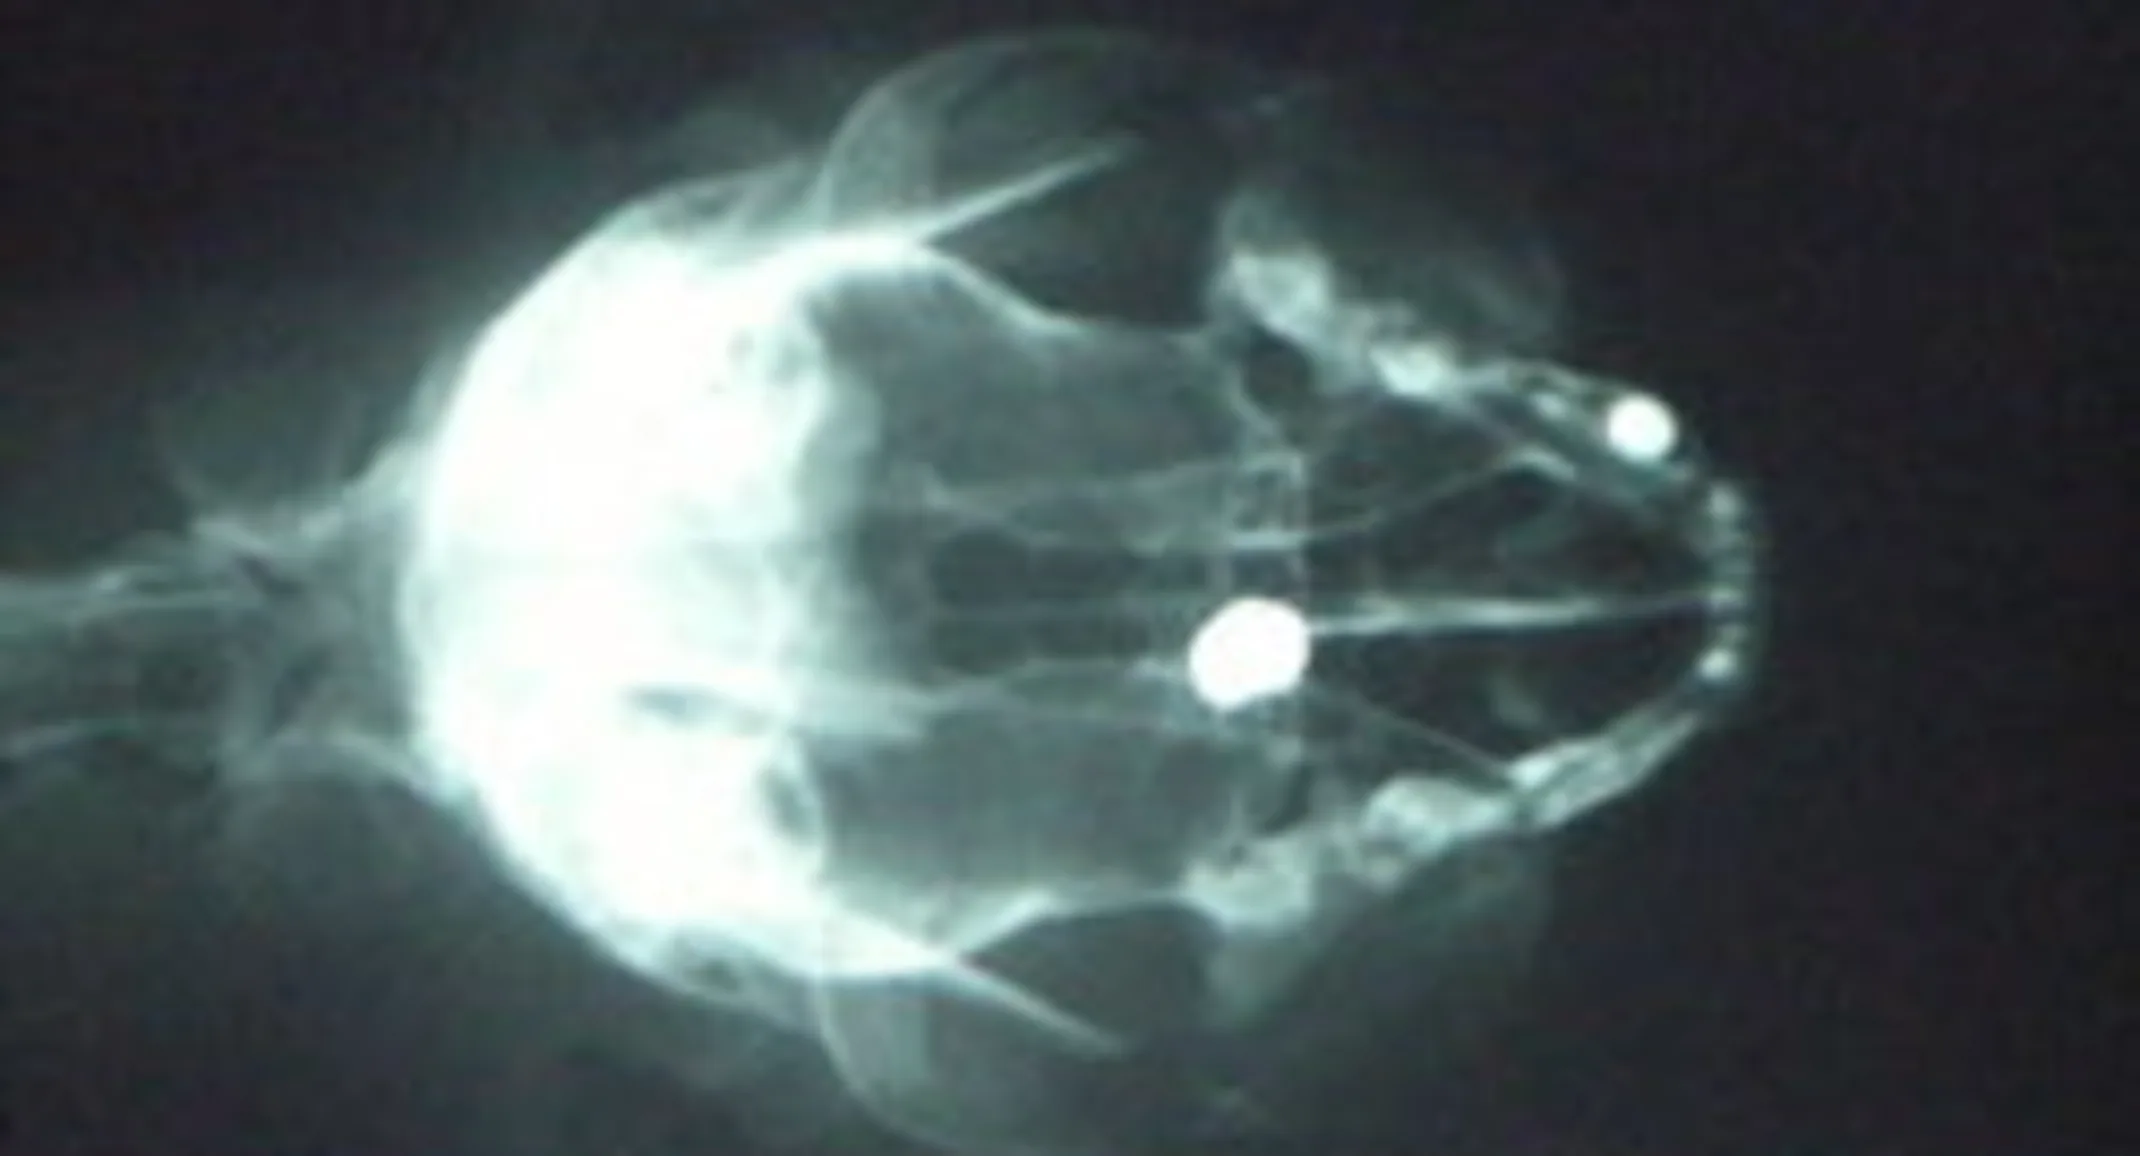

This is one of the radiographs (x-rays) we took of Tiddy Tat’s skull prior to the Rhinoscopy clearly showing a small round object in the middle of her skull.

During the Rhinoscopy (using the small endoscope camera to examine the interior of the nose and the back of the throat area), this is what we saw as we entered the nose towards the back of her skull. This metallic object was seen lodged in the very back of her nasal canal. The object was only a few millimeters away from a section of bone called the cribiform plate that separates the nasal canal and sinus from the brain.

The metallic object was covered in white mucous and scar tissue due to being lodged for so long. The object was removed with the endoscope and small endoscopic grasping forceps.